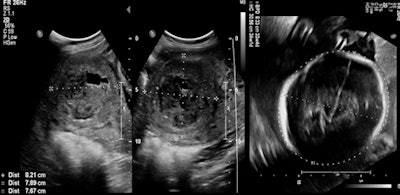

الأورام الليفية الرحمية عبارة عن أورام حميدة في الرحم يمكن لها أن تتسبب في إطالة فترة وغزارة نزف الدورة الشهرية والذي قد يكون شديداً في بعض الحالات لدرجة أنه يسبب فقر دم ويتطلب نقل دم للمريضة و اعطاء حقن الحديد.

كما قد يعاني مرضى الأورام الليفية الرحمية من ألم في الحوض يمكن أن يعيقهم عن ممارسة حياتهم اليومية، إحساس بالضغط في الحوض، تكرار التبول، ألم أثناء الجماع، إجهاضات، تأثير على الإنجاب، كما أنه قد يسبب ضخامة كبيرة في الرحم تشبه الحمل.

لوحظ أن خطورة الأورام الليفية الرحمية على الحمل ونوع الاختلاطات الناجمة له علاقة بحجمها، عددها، ومكانها. بالتأكيد فإن العقم يحدث عندما تكبر الألياف لدرجة تتسبب فيها بإغلاق أحد أنبوني فالوب أو كلاهما او عندما يملء الرورم جوف الرحم.

بالإضافة لما سبق فإن الأورام الليفية الرحمية تترافق بنسبة عالية من الإجهاض عندما تنمو وتكبر داخل جوف الرحم الذي هو مكان انغراس الجنين (تحت المخاطية، أو داخل جوف الرحم).